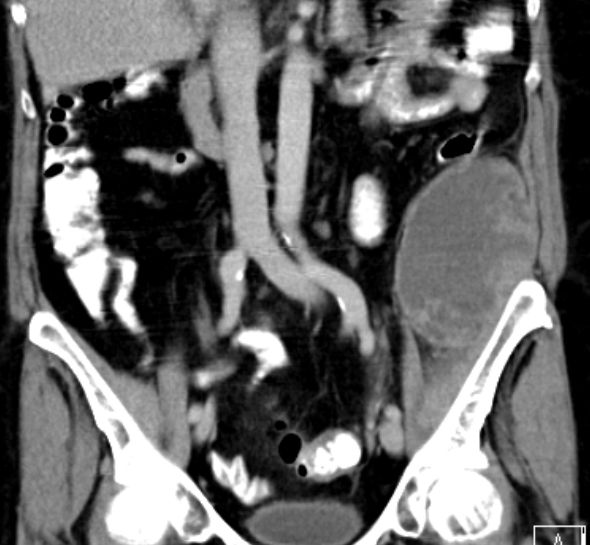

| Diagnostik | partiell nekrotisches, pleomorphes undifferenziertes Sarkom der Bauchwand.![]() |